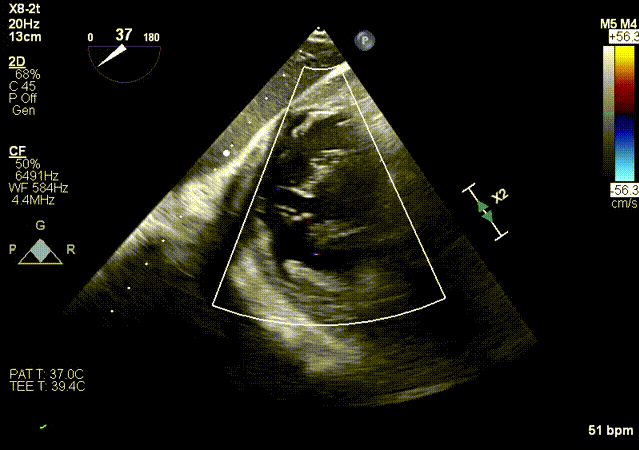

2.超声X-Plane以及实时3D下观察输送系统头端指向目标靶位。

X-Plane